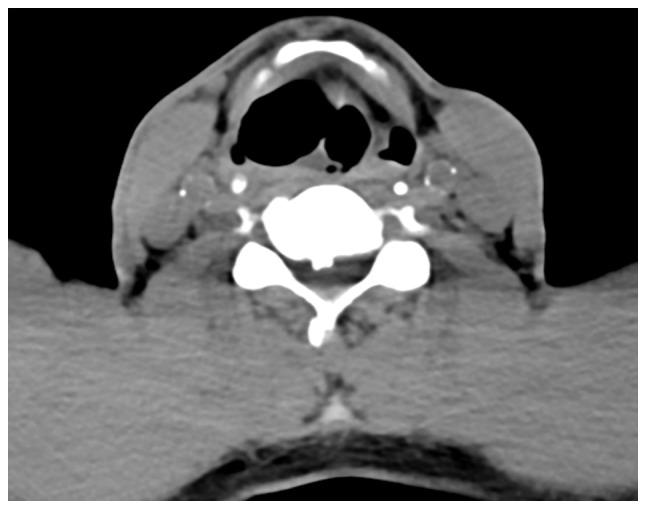

Laryngocele is a rare clinical condition characterized by an abnormal dilation of the laryngeal saccule. The present study focused on two separate cases of diagnosed patients. The first patient suffered from internal laryngocele and complained of hoarseness for almost 1 year. Plasma was used to treat the internal laryngocele and the outcomes were satisfying. The patient did not undergo any tracheostomy due to previous endoscopic surgery. The second patient included in the present study was diagnosed with mixed laryngocele and complained of swelling on the left side of the upper aspect of the neck with considerable pain for >1 month. The patient was prepped for excision by an external transcervical technique under general anesthesia. None of the two patients had any recurrence or other changes during follow-up. The purpose of reporting these two cases of laryngocele was to increase awareness of this condition. Surgery is still the first-line treatment for diagnosed cases, but with the advent of new microscopic techniques, the use of plasma in an inter-pharynx setting has become more common. The results observed after using plasma to treat one internal laryngocele may be relevant to better understanding the application of this method and confirm that it may be a new suitable approach to treat this condition.

喉膨出是一种罕见的临床病症,其特征为喉囊异常扩张。本研究聚焦于两例确诊患者。首例患者患有内喉膨出,主诉声音嘶哑近1年。采用等离子体治疗内喉膨出,效果令人满意。由于先前的内镜手术,该患者未进行任何气管切开术。本研究纳入的第二例患者被诊断为混合型喉膨出,主诉颈部上方左侧肿胀并伴有明显疼痛超过1个月。该患者在全身麻醉下通过外部经颈技术准备进行切除术。两名患者在随访期间均未出现任何复发或其他变化。报告这两例喉膨出病例的目的是提高对该病症的认识。手术仍然是确诊病例的一线治疗方法,但随着新的显微技术的出现,等离子体在咽内环境中的应用变得更加普遍。使用等离子体治疗一例内喉膨出后观察到的结果可能有助于更好地理解该方法的应用,并证实它可能是治疗这种病症的一种新的合适方法。